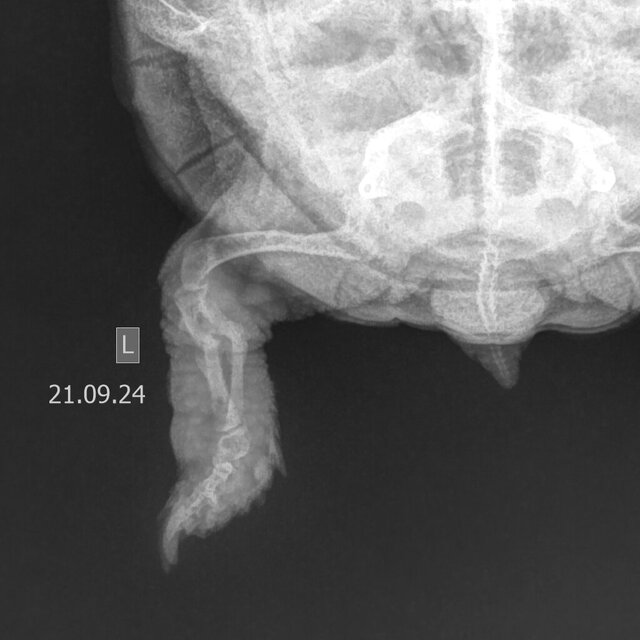

Пожалуй можно подвести черту под нашей эпопеей со сломанной лапой.

В конце июля сняли нам конструкцию именуемую остеосинтезом которая на деле была набором из скрепок и иголок от шприцов:

20240705_160750.jpg

18.07.2024 905_cr.jpg

На тот момент образовалась мозоль на одной (основной) кости,но Эскин каким то образом диагностировал вновь образовавшийся остеопороз и посему оставил нам гипс ещё на месяц.

Месяц назад повязку сняли.Мозоль по прежнему только на одной кости,но мозоль "уверенная")

Филипп пооюещал что и вторая срастётся.

Дуська на улице довольно бодро ходила и с одной костью,сегодня поехали на контрольный рентген в Джунгли".

Вторая кость тоже срослась.Кривенько конечно,но главное без ампутации обошлось,тут уж не до прямоты,проживём и без балета)

Очень надеюсь что на этом эпопея закончилась,Дуська бегает "как молодая")

Проекция левой задней конечности.JPEG